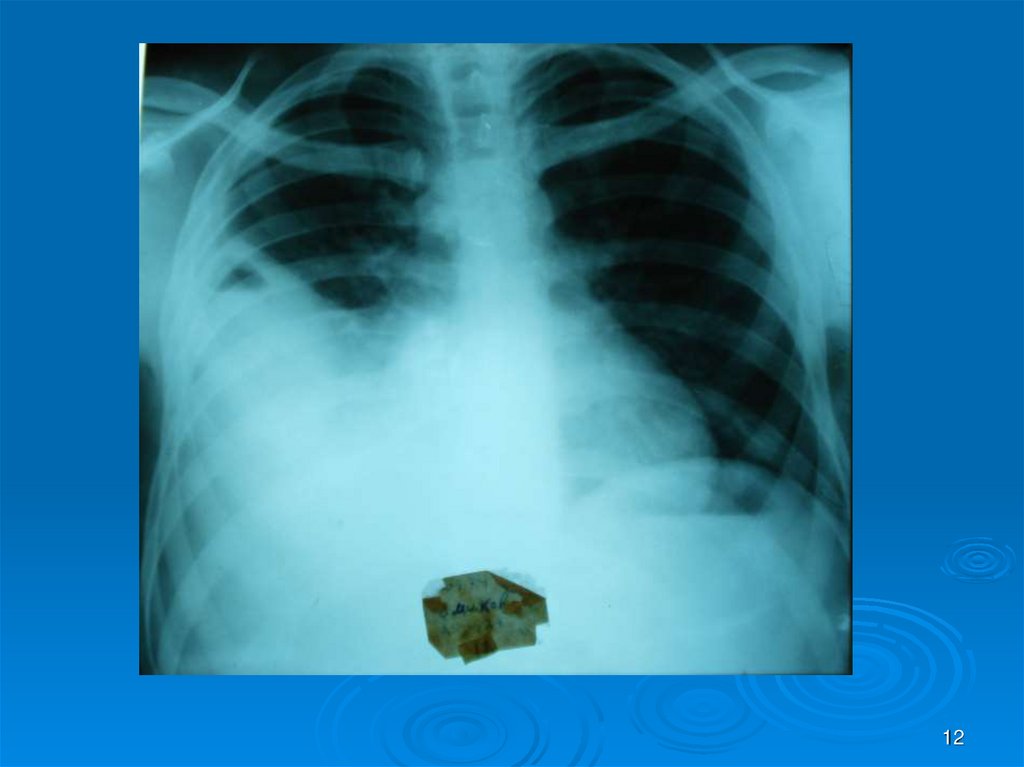

12.

12